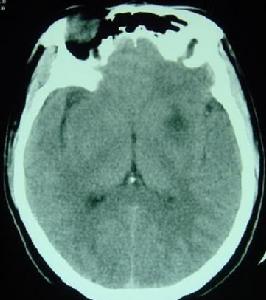

(二)顱腦外傷及腦腫瘤(craniocerebral trauma and cerebroma)

用於急性顱腦外傷及腦手術後的藥品2.顱腦腫瘤:可因腫瘤部位、性質及生長的速度不同而表現不同程度的意識障礙。急性發展的腦腫瘤,隨著腫瘤的迅速增長和顱內壓的增高,表現反應遲鈍、意識模糊、情感淡漠、嗜睡、注意力不集中等,嚴重時出現意識混濁直至昏迷。其中以額葉、胼胝休、垂體和間腦腫瘤引起嗜睡狀態者為多。間腦腫瘤以嗜睡狀態為其特徵,其嗜睡常呈發作性不可抗拒的睡眠狀態,發作時可伴有短暫的肢體無力,可在病人大哭或情緒波動時所誘發。除嗜睡狀態外,常伴有發作性意識障礙或意識喪失,這種意識障礙發作時出現肌肉過度強直,頭向後仰等。聶葉腫瘤時常以鉤回發作為其特點,發作前常有味及嗅幻覺為先兆。爾後意識模糊,常有夢境般的體驗,並有舔舌,吮唇等自動動作。顱腦腫瘤的特點為:①具有顱壓增高的症狀:頭痛、嘔吐、視乳頭水腫。②具有神經系統定位陽性體徵。③有意識障礙和其他精神症狀。④腦脊液、腦電圖和CT檢查可確定腫瘤的部位和性質。